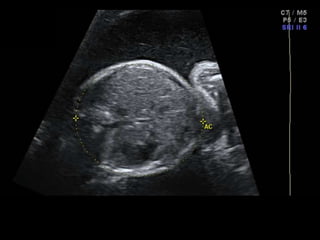

โ€ข 36 yo female 30.5 weeks pregnant

โ€ข Referred with โ€žmultiple fetal anomaliesโ€Ÿ for

fetal ultrasound

LUS โ€“ Cephalic

POSTNATAL BABYGRAM

-Cephalic

-Heart - right side

-Stomach โ€“ right side

-Liver โ€“ left side

-Des colon โ€“ right side

Situs Inversus Totalis

โ€ข 3-5% with cardiac abnormalities

โ€ข 25% with primary ciliary dyskinesia (PCD)

โ€“ Kartagenerโ€Ÿs Syndrome

Esophageal Atresia

โ€ข Polyhydramnios

โ€ข small / absent stomach if no

fistula

โ€ข Often other assoc anomalies